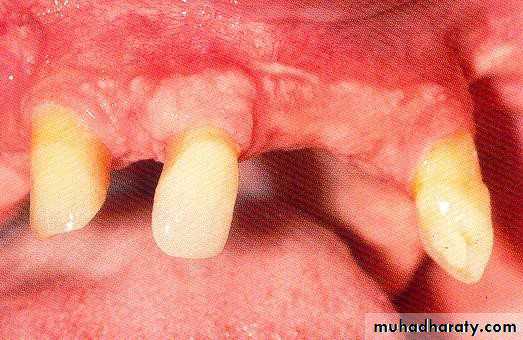

• 1) Few remaining teeth or teeth with an unfavourable distribution in the arch which precludes treatment with a removable P.D.

• 2) Severe loss of periodontal attachment in a patient who cannot afford a fixed partial denture

• 3) Complicated functional and aesthetic conditions due to tooth migration which make restoration with a removable or fixed partial denture difficult.

• 1) Bilateral distribution (avoid unilateral and diagonal).

2) Natural teeth orimplants as antagonists.

• 3) Endodontic treatment

• possible.• 4) min. 5mm periodontal

• attachment• min. 3mm attached gingiva.

• min. 2-3mm abutment height.

• no bony undercuts interfere

• with the insertion.

• 5) sufficient space between the abutment

• and the opposing.• 1) Long (6-8mm):